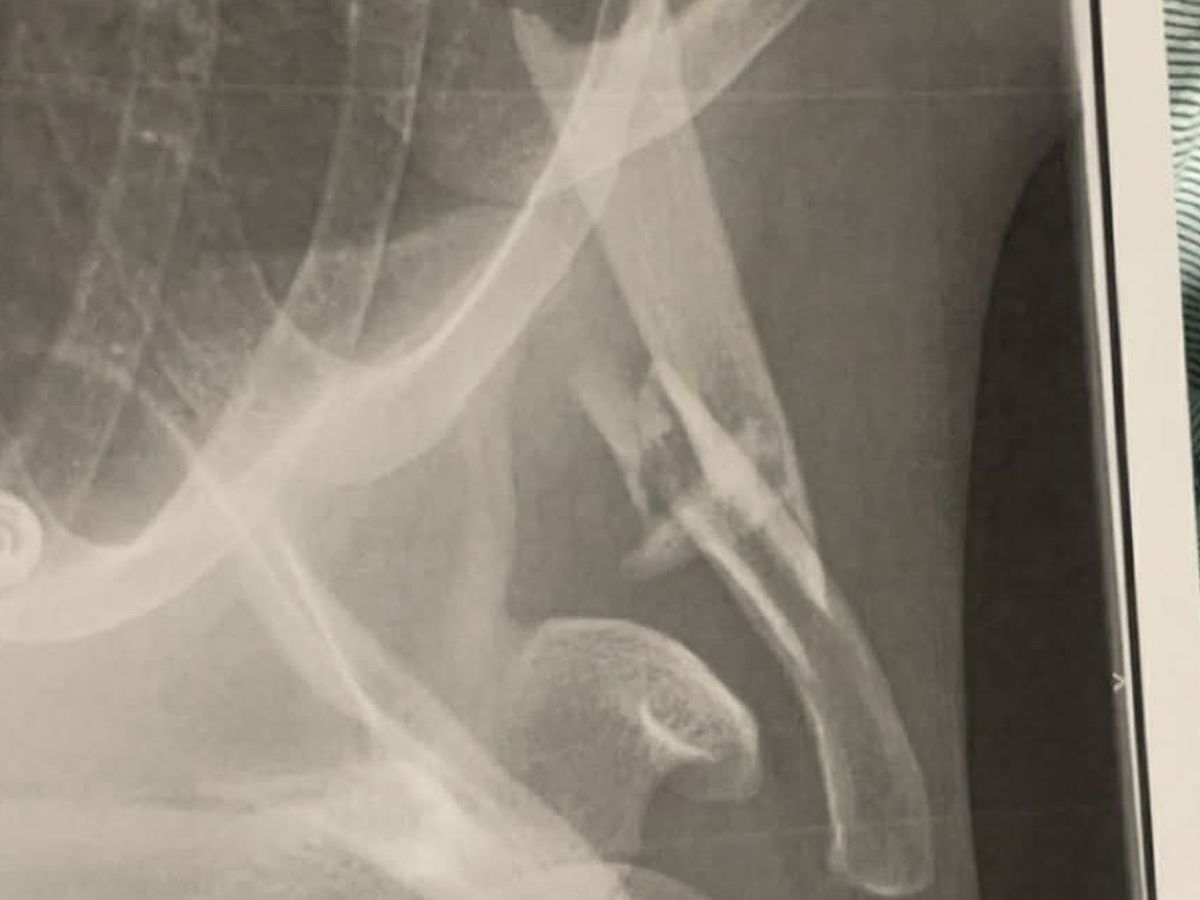

During the jump, he suffered a severe injury, breaking his clavicle bone which will require surgery the following morning. The recovery process will take 2/3 months. Between lost income, medical bills, surgery costs, and ongoing recovery expenses, the financial burden is becoming overwhelming.